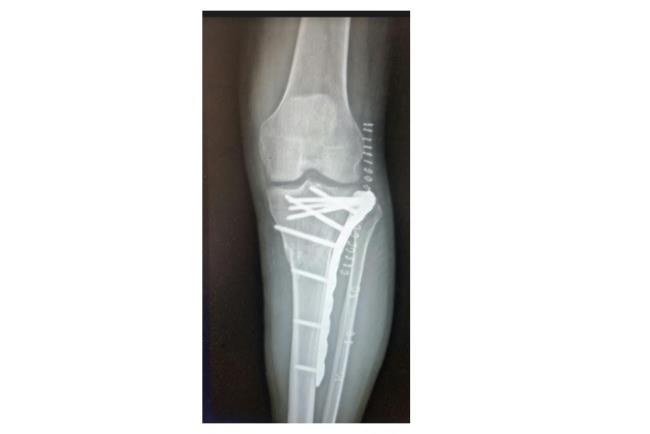

בשלב הראשון יתבצע צילום רנטגן. אם עולה חשד לכך שהשבר מערב גם את המפרק תתבצע גם בדיקת CT לשם הדמיה תלת ממדית של האזור הפגוע וחלקי השבר אותם יש להרכיב כדי להשיב למפרק את תנועתו התקינה. לרוב, כדי לטפל בשברים מורכבים יתבצע ניתוח ולא קיבוע בגבס.מטרת הטיפול בגבס היא קיבוע המצב הקיים ועל כן במקרה של שבר מורכב טיפול זה לא יועיל בהשבת התפקוד המפרקי. לכן, כדי להשיב את המצב לקדמותו יש צורך בפתיחת המפרק, העמדת כל אחד מחלקי העצם במקומו וחיבור החלקים אחד אל השני. הניתוח והקיבוע נעשים ע"י פלטות ברגים ומסמרים תוך לשדיים העשויים טיטניום או סוג של פלדת אל חלד.

קיבוע שבר בעצם הטיביה | באדיבות פרופ' דורון נורמן